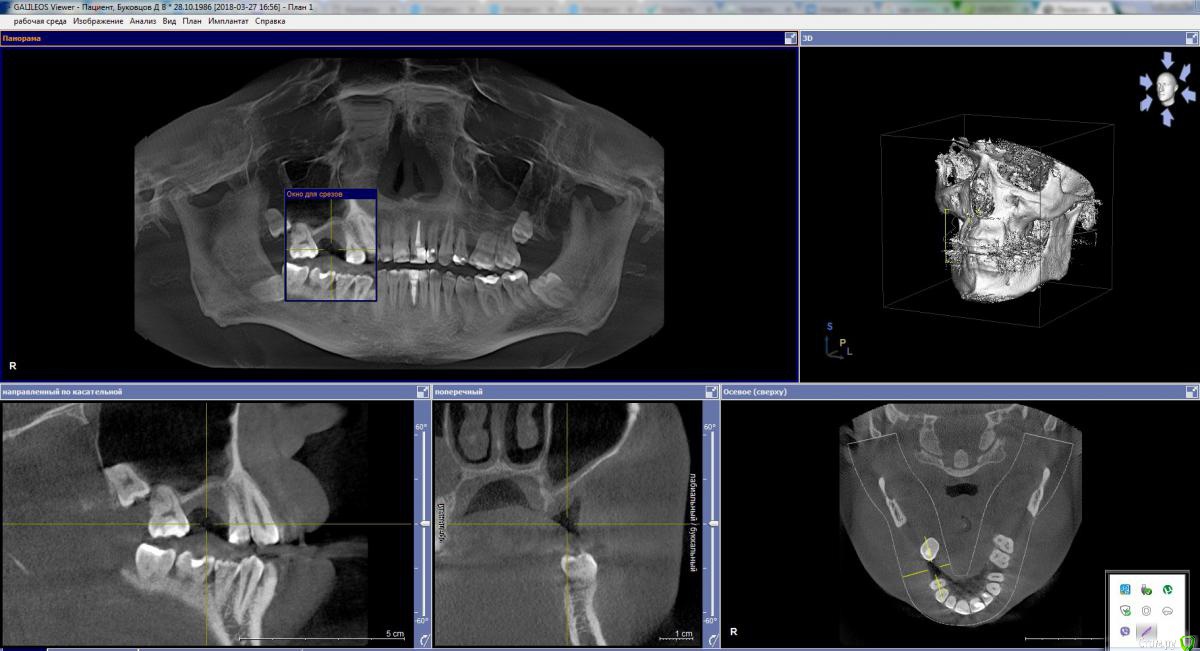

20.01.18 удалил зуб у хирурга-имплантолога, с которым планировал дальше работать по имплантации. Договорись с ним, что я приду через 2 месяца, когда место удаления заживет и будем дальше решать что делать. Пришел к нему на приём 27.03.18, сделали челюстно-лицевую КТ, на основании которой он сказал, что собственной кости у меня, для вживления импланта очень мало (у меня где-то 1-2 мм, а нужно 6-8 мм толщины кости) и шансов на положительный исход операции по установке импланта (синус-лифтинг) немного. Посоветовал "смотреть" в сторону установки моста.

Прикладываю фото челюстно лицевой компьютерной томографии (https://cloud.mail.ru/public/LD9V/B5PutrmUS) . Ссылка для скачивания архива самой томографии:  https://cloud.mail.ru/public/3Bh2/J9rb61XX4   ( сделана в программе Galileos). Если нужно, могу выложить образ диска для виртуального привода.